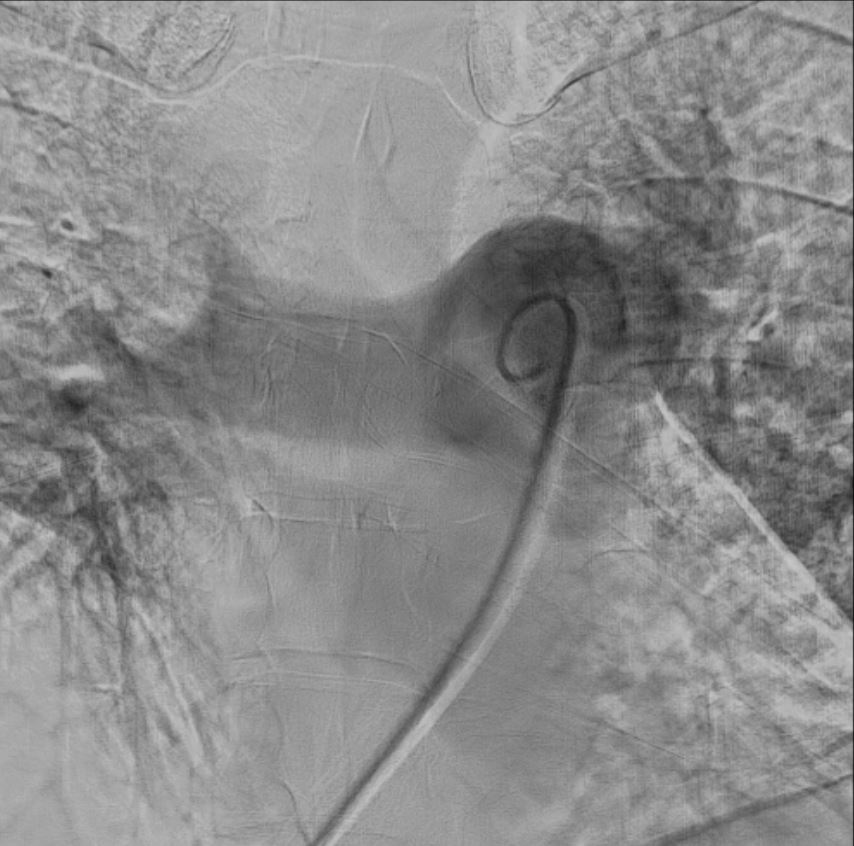

Right femoral vein access was obtained under ultrasound and fluoroscopy guidance. A 6Fr multipurpose (MP) catheter was used to deliver a J-tip guidewire into the main pulmonary artery, which was then exchanged for a pigtail catheter. Digital subtraction angiography revealed filling defects in the truncus anterior and bilateral interlobar arteries. The 6Fr femoral sheath was upsized to a 16Fr sheath. The Penumbra ENGINE and Lightning Flash 2.0 system, with a 16Fr aspiration catheter, was primed. Using the MP catheter, the J-tip guidewire was delivered into the left pulmonary artery and exchanged for the 16Fr aspiration catheter. Multiple aspiration runs were performed using the computer-assisted vacuum thrombectomy system. The same steps were repeated for the right pulmonary artery. The procedure lasted 2 hours, with 1.2L of blood loss and approximately 6-8 cubic centimeters of fresh clots aspirated. The patient received 2 units of packed red blood cells during the procedure. Femoral access was closed with a figure-of-8 suture.